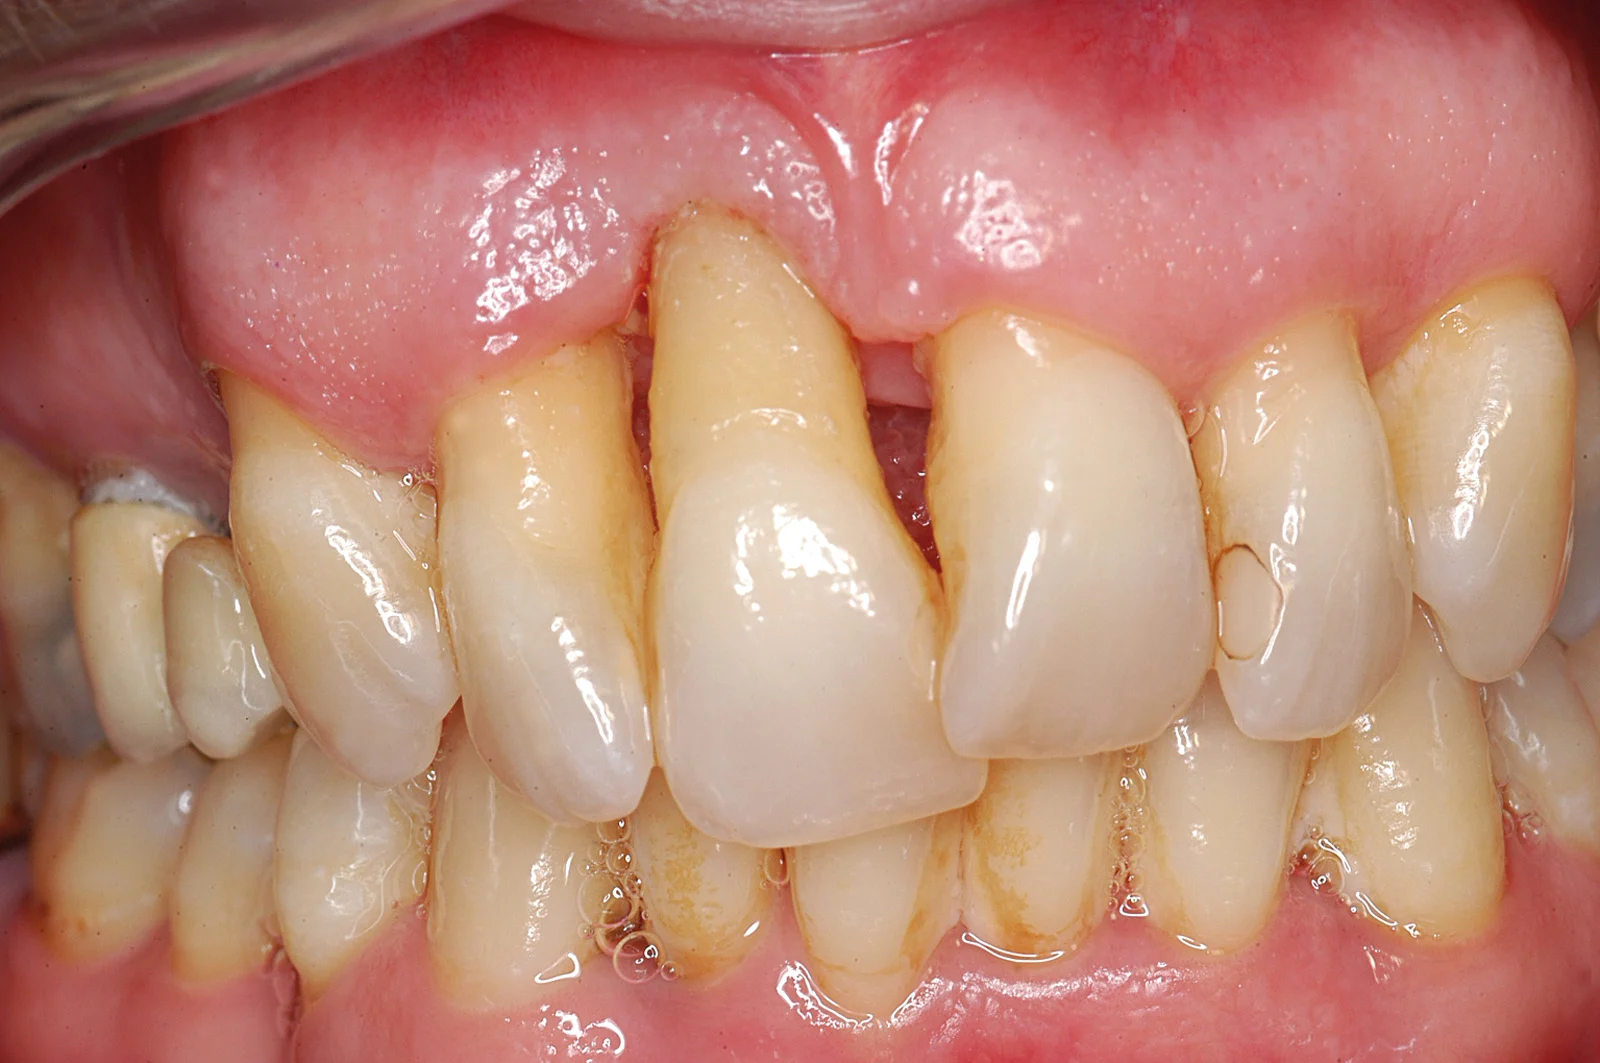

Cause principali del riassorbimento osseo: edentulia, parodontite, traumi

Edentulia prolungata: la mancanza di un dente per mesi o anni comporta la perdita graduale del supporto osseo.

Parodontite avanzata: l’infiammazione cronica delle gengive può distruggere l’osso alveolare che sostiene i denti.

Traumi dentali o chirurgici possono danneggiare direttamente l’osso o comprometterne la vascolarizzazione, causando riassorbimento.